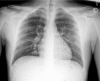

Coronavirus 2 (SARS-CoV-2) is now considered a pandemic causing Coronavirus disease (COVID-19), multiple fatalities and morbidities which have been associated with it worldwide. We report a severe pneumonia causing acute respiratory distress syndrome due to a coinfection with SARS-COV-2 and Parainfluenza 4 virus in a Hispanic 21 year old male in Florida, USA. The case represents the importance of prompt diagnosis and awareness of the potential co-infection with other respiratory viruses and this novel deadly virus.